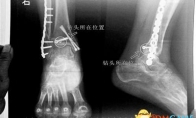

胡女士的腿部X光图看着X光片中自己腿内的异物,胡女士就感到莫名的担忧。胡女士于2013年3月在北京市丰台区右安门医院进行了一次骨折手术,术后医生才发现手术时用来打眼用的钻头不慎遗留在了胡女士的骨头中,并且无法取出。“这就是医院的责任。”胡女士说,春节后她已经与右安门医院进行交涉,索赔12万元。而右安门医院至今没有与胡女士达成一致,院方负责人称钻头被遗留属于手术的医疗风险,是双方共担的。此外,不锈钢材质的钻头在体内并不会产生多大的危害。缘起术后钻头被遗留在腿里近日,在丰台区右安门医院,北京青年报记者见到了胡女士,她走起路来显得一瘸一拐,腿脚并不利索。在她带来的X光片上,可以清晰地看到,有一个异物存在于腿内部。“就是去年3月的那场手术。”胡女士的老伴方先生回忆说,20